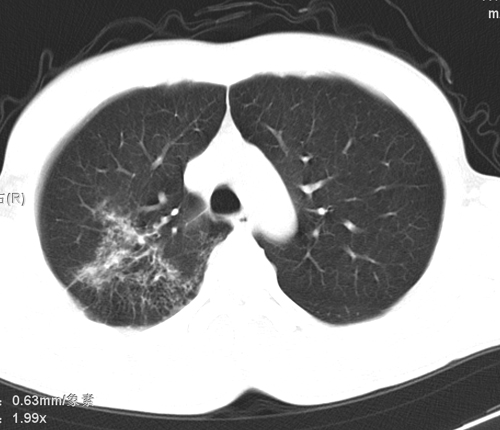

标题: CT24548:男 31 咳嗽 咯血一天 行CT检查 [打印本页]

标题: CT24548:男 31 咳嗽 咯血一天 行CT检查

ct考虑结核 但化验结果示白细胞总数 淋巴均正常,血沉7mm/h不快,请看看结核 支扩还是其他

右肺上叶尖端,后段下叶背段结核伴空洞形成

右肺继发性肺结核伴空洞形成!

右肺继发性肺结核伴右肺下叶背段空洞形成。